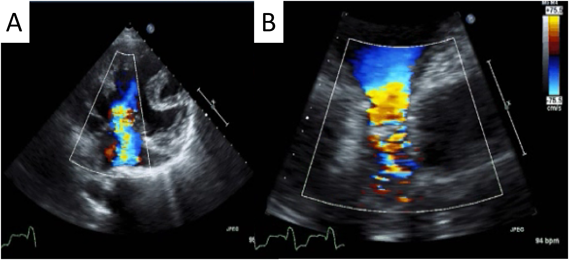

胸部X線写真

心胸郭比(Cadiothoracic ratio: CTR)71%の心拡大と,肺うっ血所見を認めた(Fig. 1A).

Fig. 1 Preoperative chest X-ray and electrocardiogram

(A) Preoperative chest X-ray. (B) Preoperative electrocardiogram.

心電図検査

心拍数は95/分の洞調律で,右室肥大所見を認めた.QRS幅は210 msecと広く,右軸変異を認めた(Fig. 1B).前医での24時間心電図上は20~30秒程度持続し自然復帰する心拍数140~160 bpmの発作性上室性頻脈を認めた.